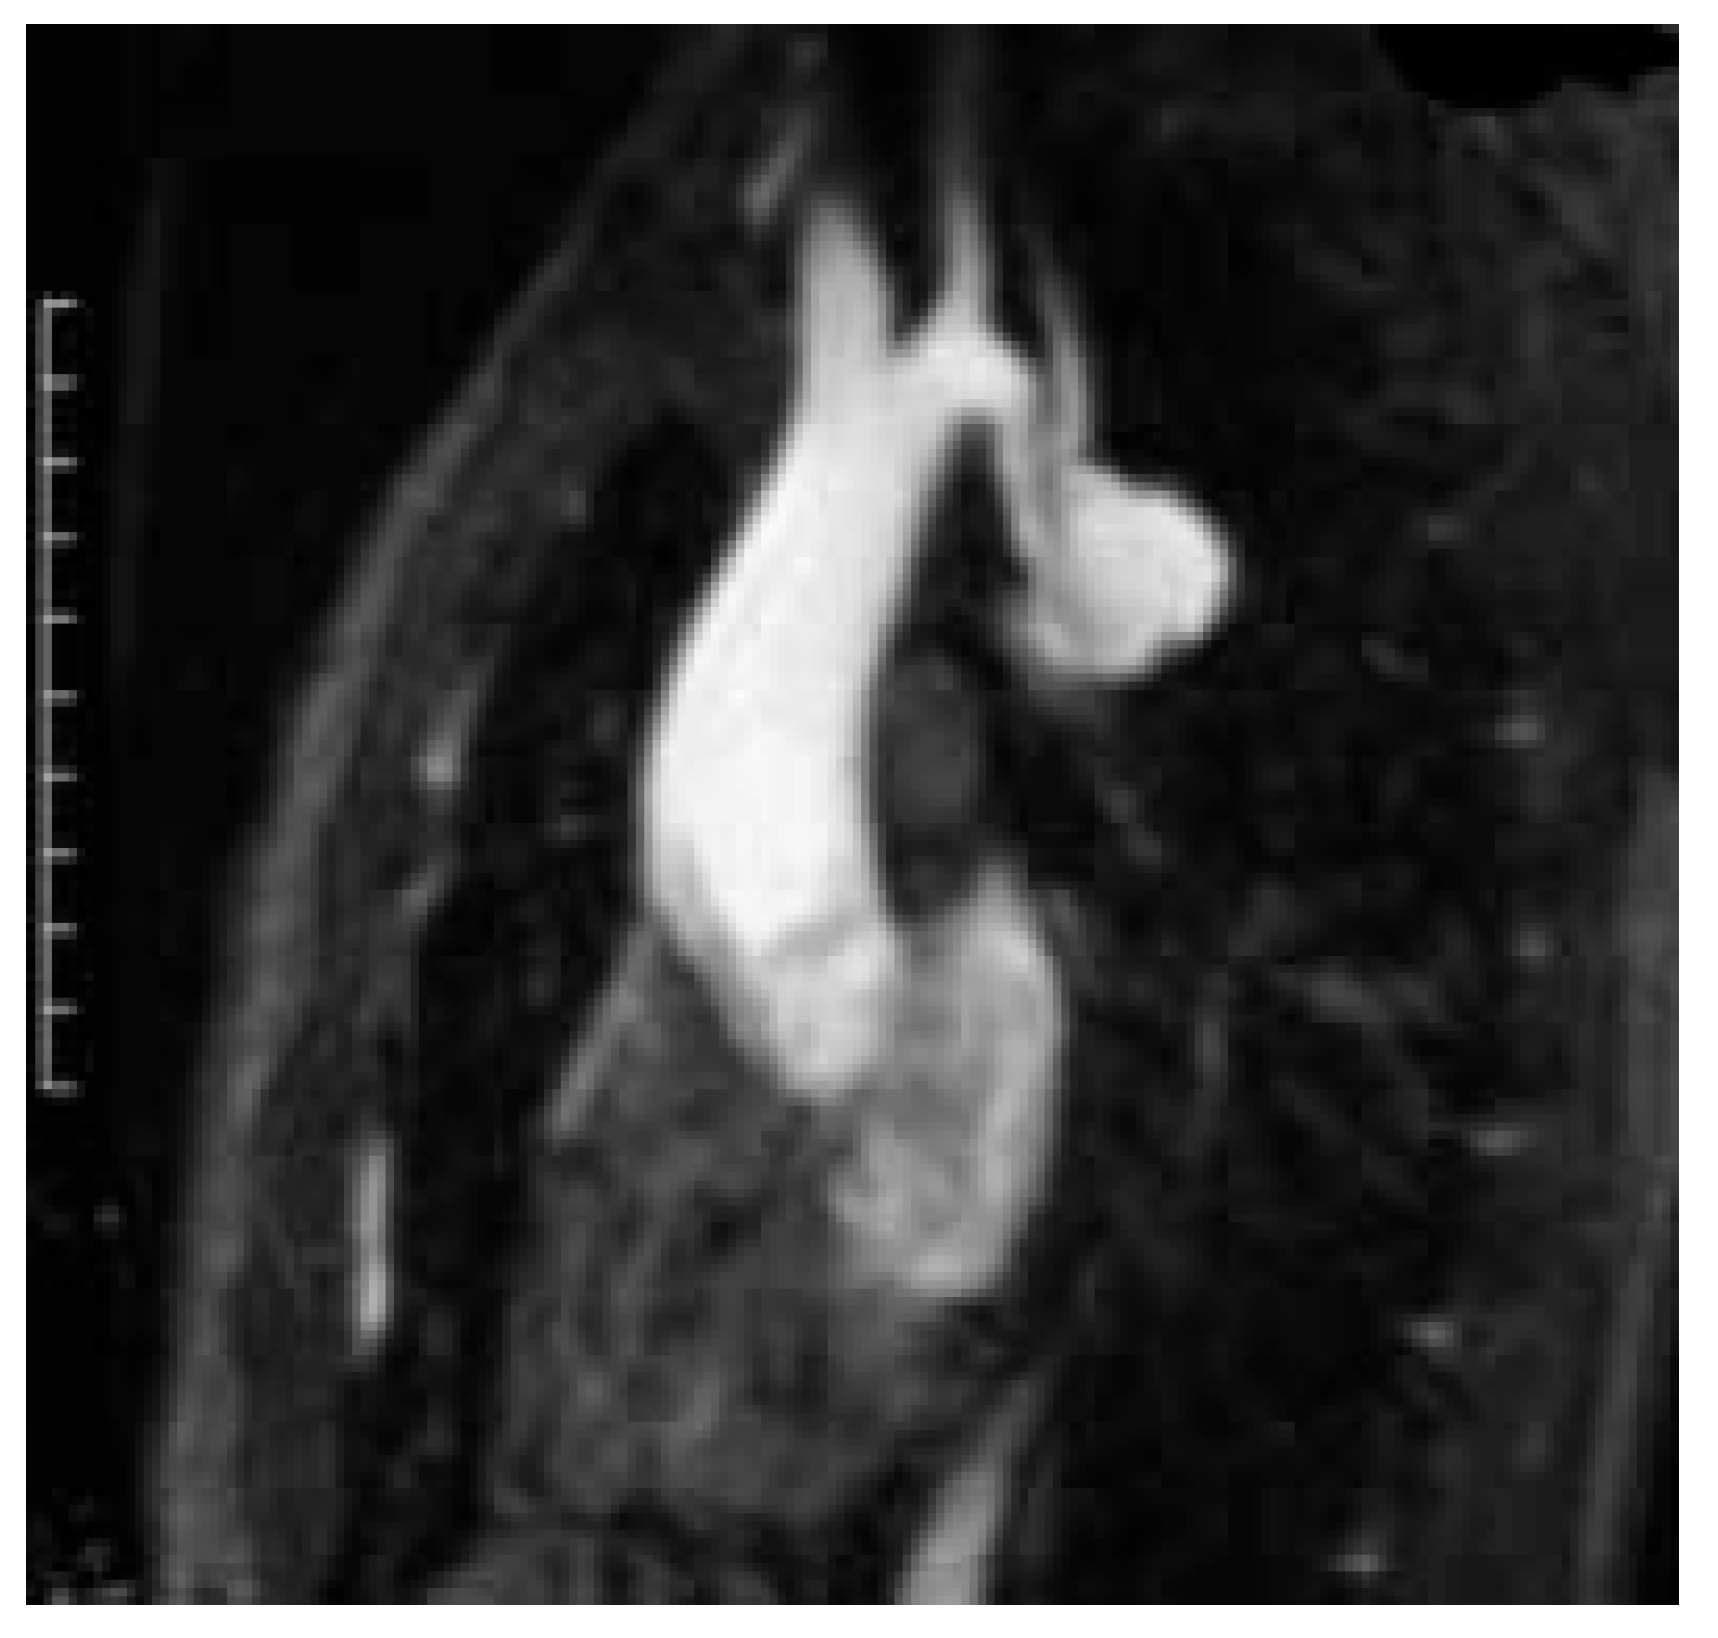

Arteriography confirmed proper position of the stent graft and complete exclusion of the lesion at the end of the procedure. CT-scans were performed in every patient before discharge (Figure 6). One patient had an endoleak type I and underwent successful additional retrograde stent-graft placement over the proximal landing zone three weeks following the initial procedure.

Figure 6.

Postoperative CT-scan (in patient from Figure 1) showing complete exclusion of the aneurysm in the mid-aortic arch.

Clinical follow-up extends up to 30 months and has been uncomplicated in all patients. CT-scan at 6 months demonstrated complete exclusion of the arch lesion in all cases and did not reveal any persisting endoleak.